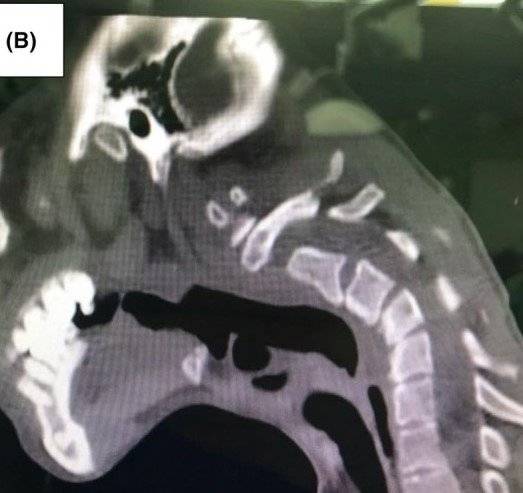

정밀 검사 결과, 경추 3~5번 부위에 휘어짐(후만측만)과 퇴행성 변화가 확인됐다. 의료진은 A씨에게 DHS 진단을 내렸다. 이는 주로 신경근육 질환에 의해 발생하는 희귀 증상이다.

A 씨의 상태는 단순한 자세 교정으로는 회복이 불가능한 수준이었다. 이에 따라 의료진은 세 단계에 걸친 대규모 수술을 진행했다. 수술 후 그는 별다른 합병증 없이 회복됐으며, 1년 뒤에는 목의 정렬도 눈에 띄게 개선됐다.